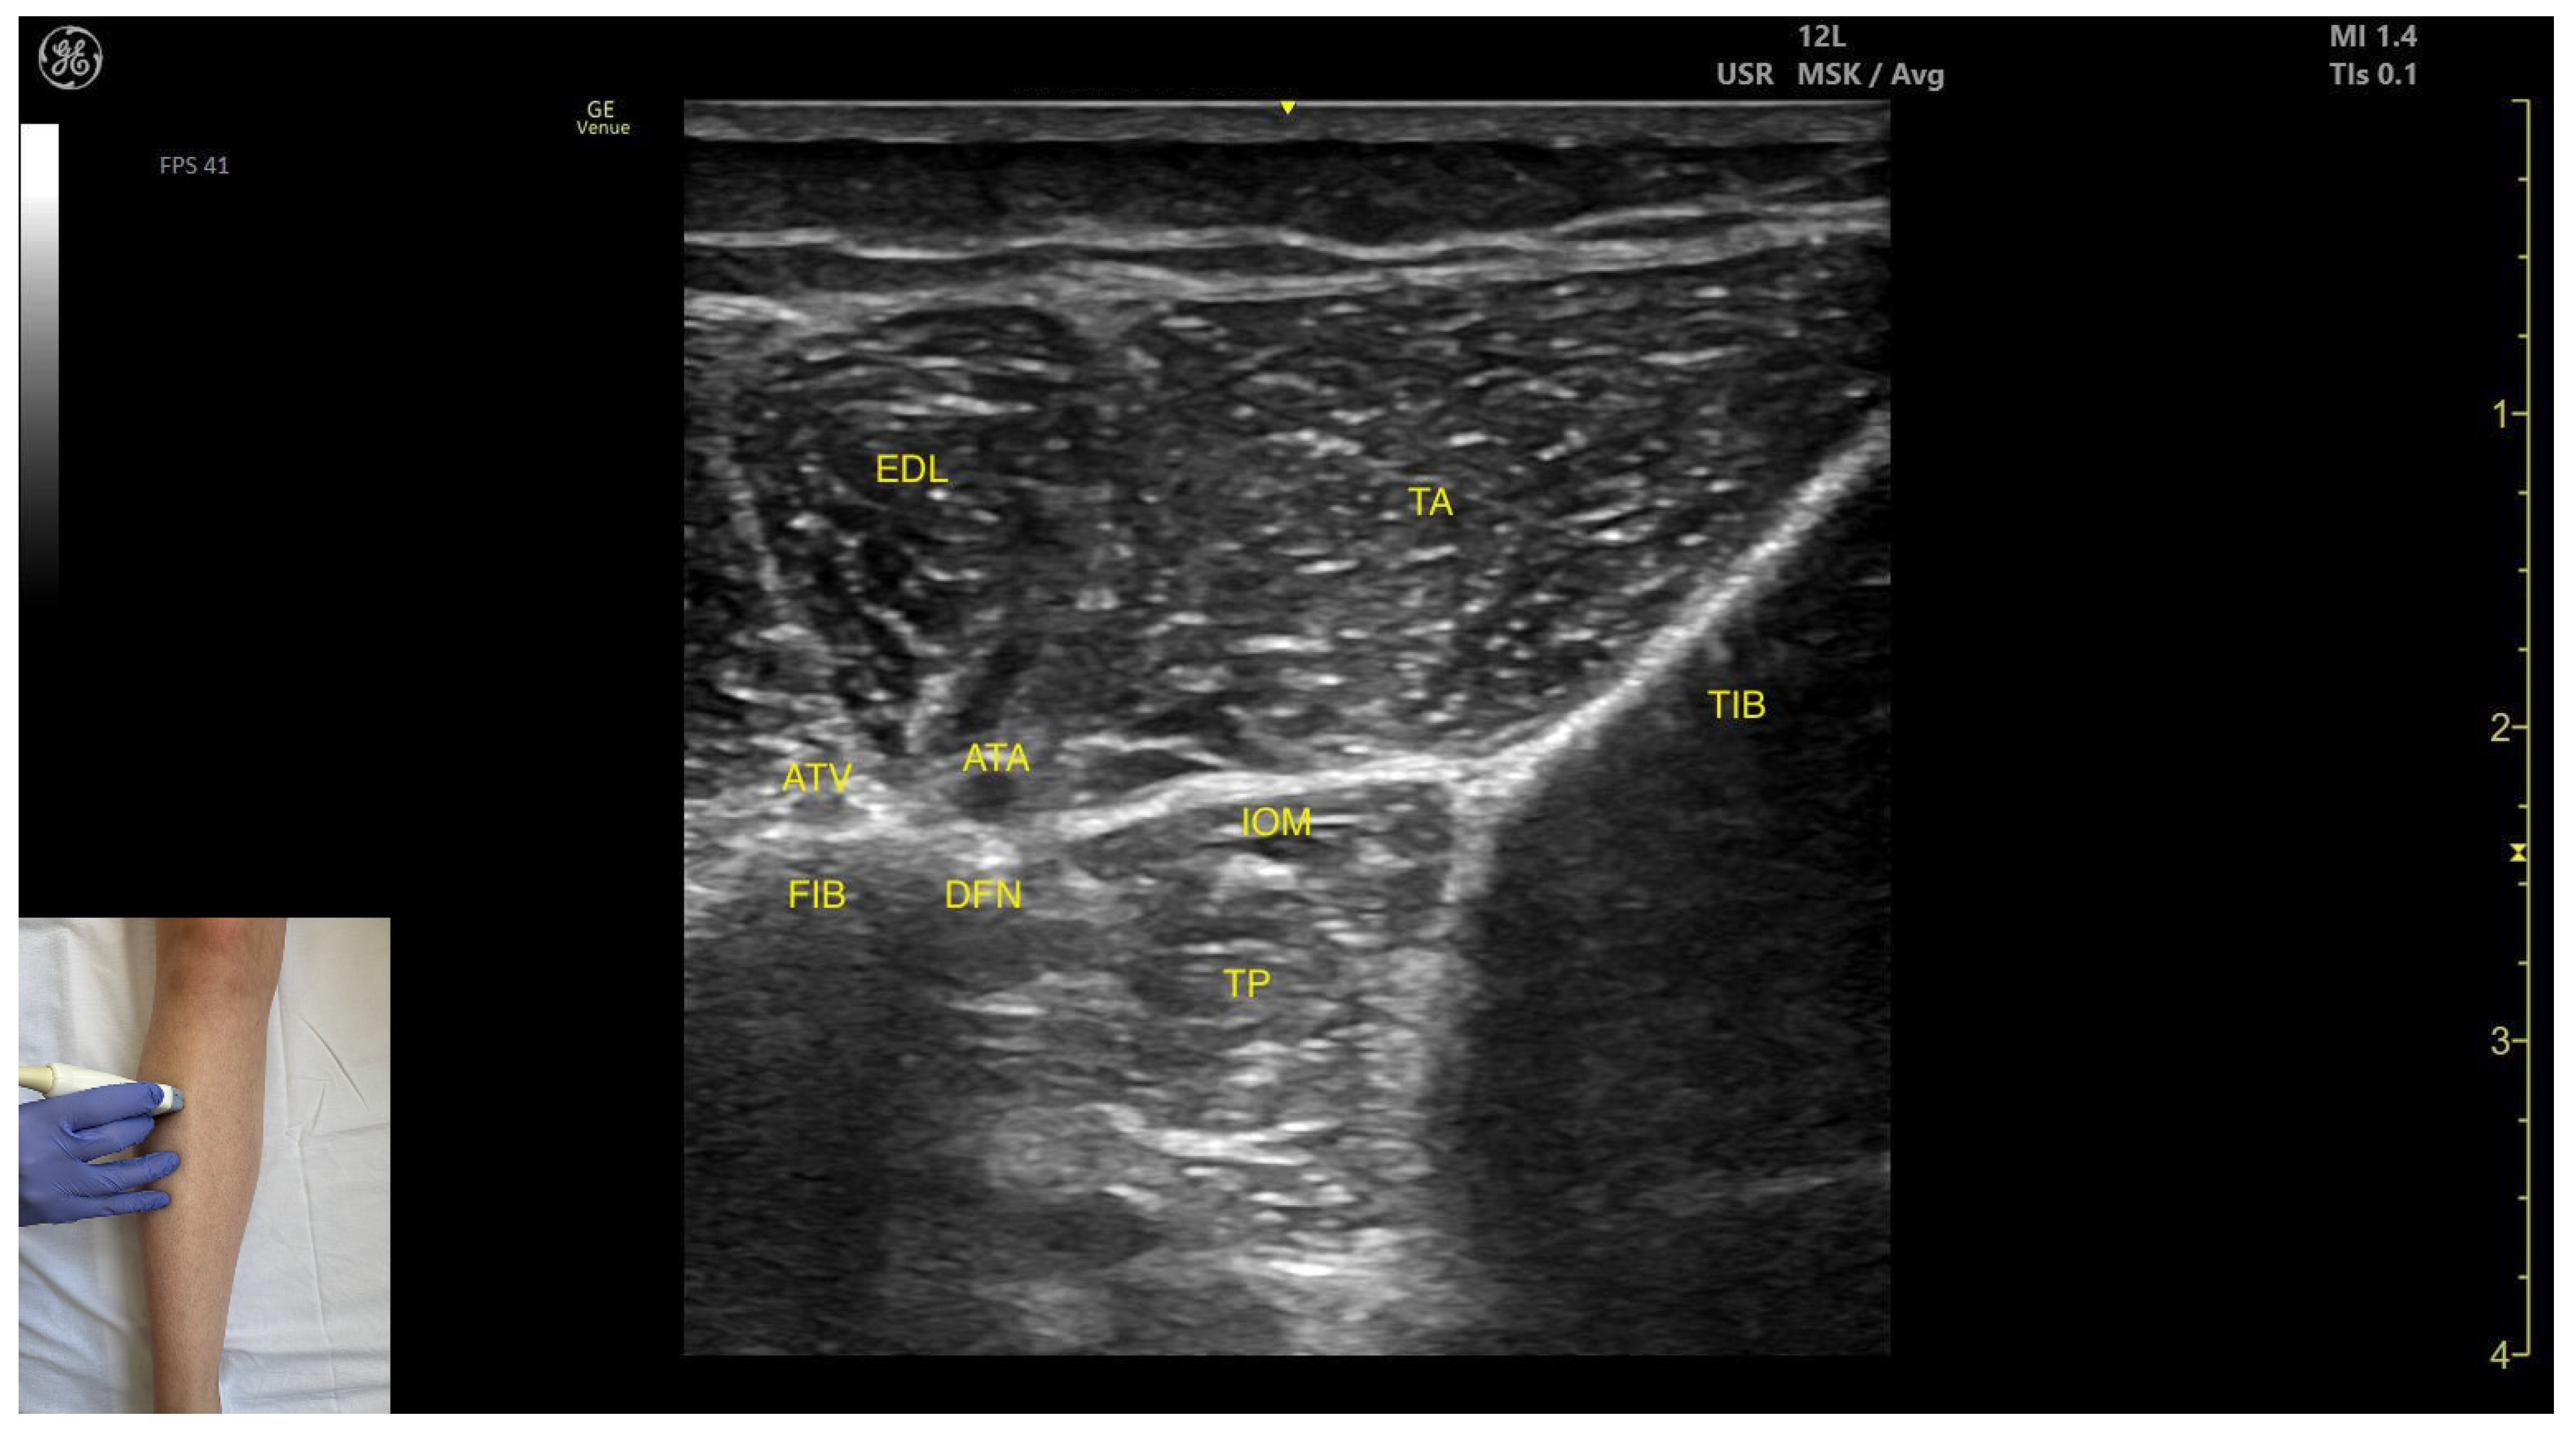

3.3.2. Anterior Window

Ultrasound Identification

Key Ultrasound Landmarks

- Muscle position: It is the deepest muscle in the posterior compartment of the leg.

- Neurovascular bundle: Superficial to the interosseous membrane lies the neurovascular bundle composed of the deep peroneal nerve, anterior tibial artery, and anterior tibial vein.

- External fascia: TP has a pronounced fascia that separates it from the tibialis anterior and extensor digitorum longus during BoNT-A injection.

- Dynamic evaluation: During dynamic evaluation muscle contraction is visible during inversion and plantar flexion of the ankle joint.